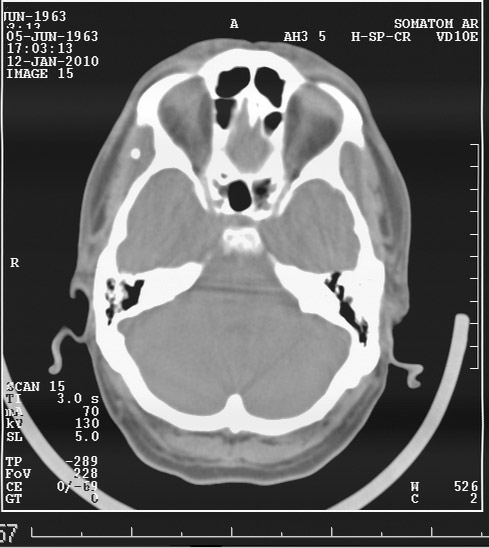

Выкладываю данные КТ

На снимке утолщение веретенообразное мышечного слоя с наличием кальцификатов(два) Кальцификаты в мышце чаще встречаются при паразитарных инфекциях(трихиниллез,токсоплазмоз,цистецеркоз),но их больше по количеству и в разных местах.Оссифицирующий миозит-имеет свою картину и распространение.Насчет Хортона-навряд ли,это же поражение сосуда.Насчет тофусов-они содержат ураты,чаще локализуются подкожно(не в мышце),при подагре осификации вдоль сухожилий.А может был удар,гематома с частичной кальцификацией?